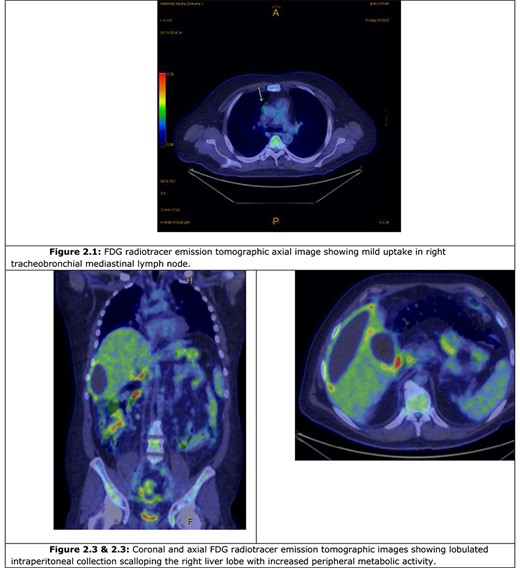

A computer tomography (CT) abdomen and pelvis with contrast was ordered (Fig. 1), which demonstrated a fluid-filled abdominal collection continuous with a distended gallbladder. The patient was referred to a local general surgeon, and underwent a positron emission tomography (PET) study to rule out intra-abdominal malignancy (Fig. 2). The differentials included primary mucinous tumour of the gallbladder, duplication cyst and pseudomyxoma peritonei.